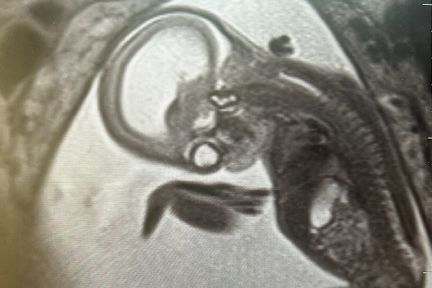

Casey was born with a clear plan in place. At just one day old, he underwent a delicate neurosurgical procedure performed by Dr. Davidson, who has extensive experience treating spina bifida and hydrocephalus in newborns.

The surgery addressed the meningocele and helped manage fluid buildup on Casey’s brain, which were critical steps to protect his neurological development.